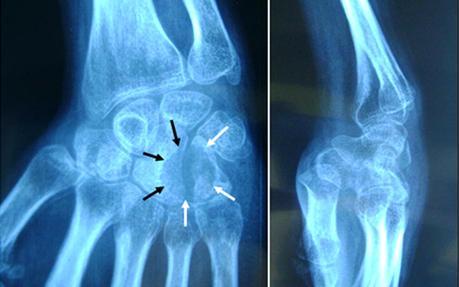

Nous rapportons ici le cas d’une jeune patiente âgée de 23 ans, étudiante, sans antécédents particuliers, qui a consulté pour impotence fonctionnelle et des douleurs du poignet droit, évoluant progressivement depuis six mois. Les douleurs étaient d’allure inflammatoire, elles sont exacerbées par la palpation d’une tuméfaction localisée au niveau de la face dorso-médiale du poignet qui est raide en inclinaison radiale (Figure 2). Toute tentative de mobilisation du poignet était extrêmement douloureuse. A la radiographie standard il existait une image ostéolytique bien circonscrite au niveau de l’hamatum mordant sur Le bord médial du capitatum (Figure 3). Le scanner a mis en évidence une lésion lytique occupant la quasi-totalité de l’hamatum avec lyse du bord médiale du capitatum, respectant les parties molles (Figure 4).